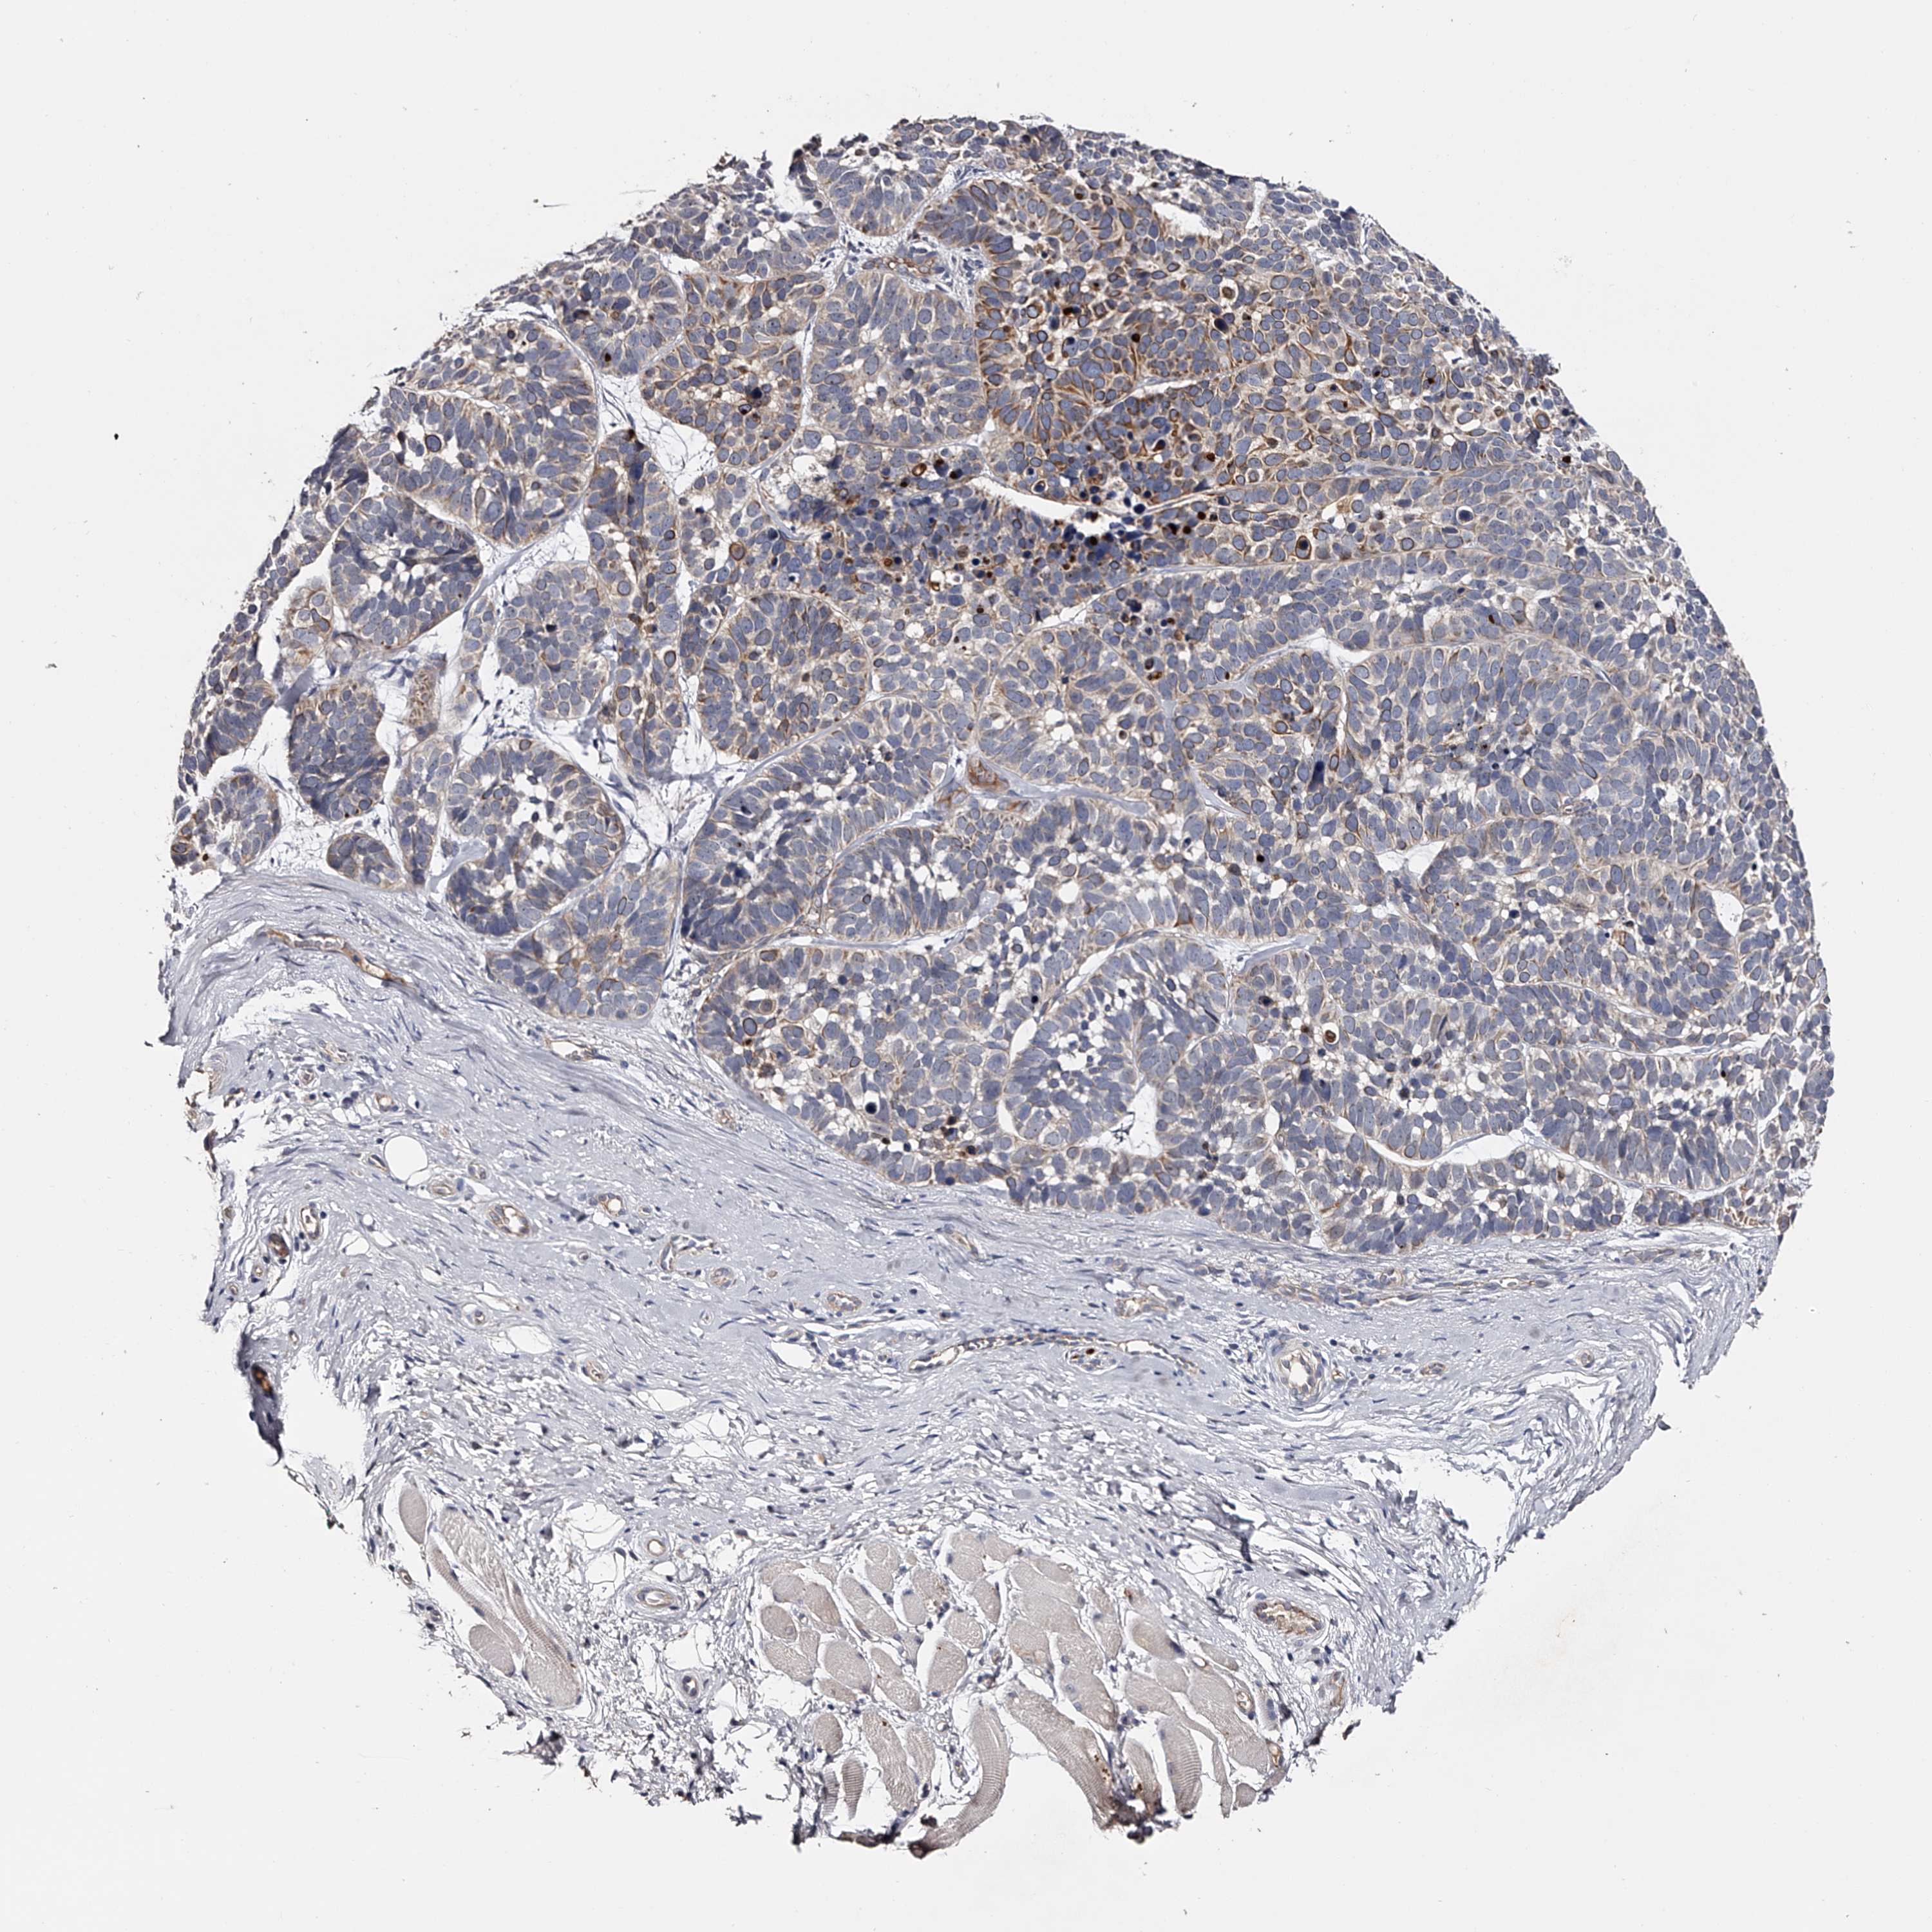

SKIN CANCER - Protein expressioni

A mouse-over function shows sample information and annotation data. Click on an image to view it in a full screen mode. Samples can be filtered based on level of antibody staining by selecting one or several of the following categories: high, medium, low and not detected. The assay and annotation is described here.

Antibody staining in the annotated cell types in the current human tissue is reported as not detected, low, medium, or high, based on conventional immunohistochemistry profiling in selected tissues. This score is based on the combination of the staining intensity and fraction of stained cells.

Each image is clickable and will lead to virtual microscopy that enables deeper exploration of all samples and also displays staining intensity scores, fraction scores and subcellular localization as well as patient and tissue information for each sample.

Antibody HPA029668

Squamous cell carcinoma, metastatic, NOS